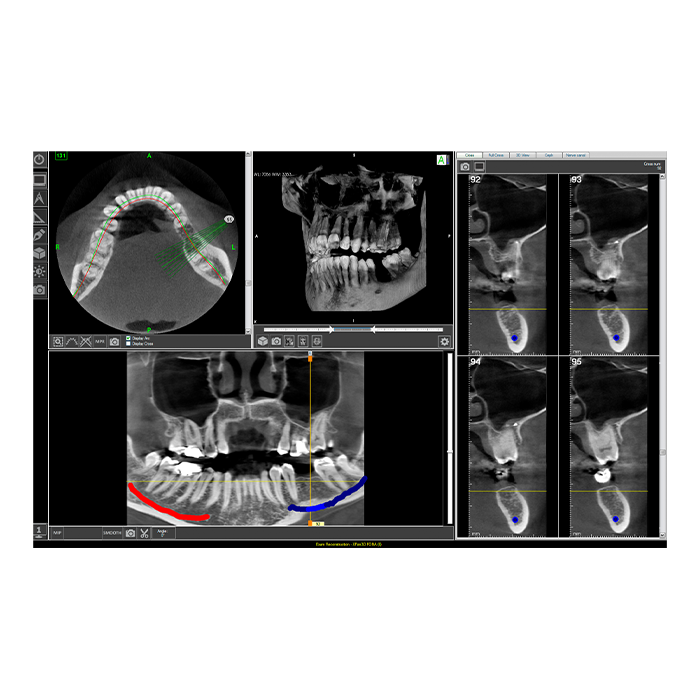

Система Fona XPan 3D представляет собой современное решение для панорамной и 3D-визуализации в стоматологической практике. Это оборудование нового поколения, которое объединяет в себе проверенную надежность панорамной съемки и передовые возможности трехмерной томографии. Система создана для того, чтобы предоставить врачу-стоматологу, ортодонту или челюстно-лицевому хирургу максимально полную диагностическую информацию для постановки точного диагноза и планирования эффективного лечения.

Fona XPan 3D — это инвестиция в качество диагностики и безопасность пациентов. Система позволяет за одно сканирование получить как обзорный панорамный снимок, так и прицельные 3D-томограммы интересующей области, минимизируя лучевую нагрузку и экономя время врача и пациента.

- Многофункциональность в одном аппарате: Одно устройство заменяет несколько. Вы получаете возможность выполнять панорамные снимки (ортопантомограммы), 3D-томографию (КЛКТ) отдельных сегментов, телерентгенографию (ТРГ) в боковой проекции, а также снимки височно-нижнечелюстных суставов (ВНЧС).

- Высокая точность и детализация: Цифровой датчик с высоким разрешением обеспечивает получение четких изображений, на которых видны мельчайшие детали: состояние корневых каналов, начальные кариозные поражения, структура костной ткани для имплантации.

- Мощное программное обеспечение: В комплекте поставляется профессиональное ПО для обработки, анализа и хранения снимков. Оно позволяет проводить измерения, строить 3D-модели, планировать установку имплантатов и легко интегрируется с другими цифровыми системами клиники.

- Хирургическая стоматология и имплантология: Точная оценка объема и плотности костной ткани, планирование синус-лифтинга и позиционирования имплантатов с учетом анатомических структур (нижнечелюстной канал, гайморова пазуха).

- Ортодонтия: Анализ лицевого скелета, положения зубов и их зачатков, планирование комплексного ортодонтического лечения, в том числе с использованием брекет-систем или элайнеров.

| Размер вокселя (3D) | От 0.08 мм до 0.3 мм (зависит от режима и области сканирования) |

| Область сканирования (3D) | Регулируемая: от небольшого сегмента (например, 5x5 см) до полной челюсти (например, 15x10 см) |

3D-снимок (КЛКТ) предоставляет объемное изображение, позволяя врачу увидеть область интереса в трех плоскостях и оценить плотность тканей. Это исключает наложение структур, что критически важно для планирования имплантации, поиска дополнительных каналов или диагностики сложных переломов.